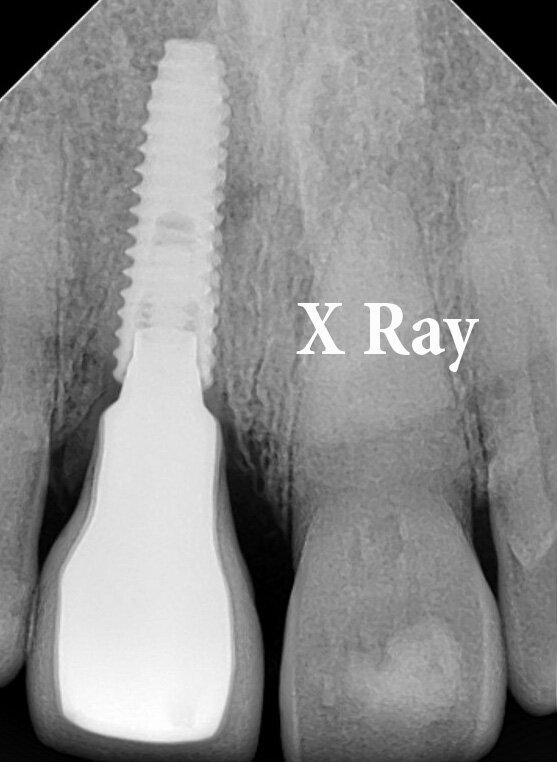

Special precautions were taken to avoid damage to the bone walls of the extraction socket. Following preparation of the implant bed in the palatal part of the root, all residual tooth fragments were completely removed. A careful curettage of the extraction socket was performed to remove granulation tissue. The buccal fragment of the root was preserved 1mm coronal to the buccal bone plate. The 4X13mm implant was placed in the palatal part of the extraction socket, without contact with the labial root portion (shield). 45 Ncm Torque was achieved at the time of implant placement. (Fig 1 - 17)

Fig 17: Radiographic documentation of implant placement